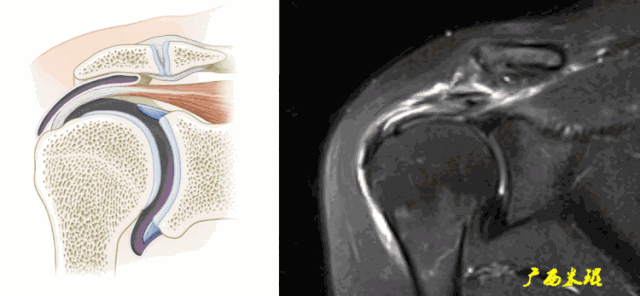

3、邻近组织异常

邻近组织异常包括信号异常和形态异常,是肩袖撕裂的间接征象,对诊断有意义但不能直接诊断肩袖撕裂。邻近组织包括肩峰下滑囊、骨(肩峰、大结节、小结节、喙突)、关节(肩锁关节、盂肱关节)、肱二头肌长头腱等。

a、肩峰下滑囊增大,是肩袖损伤必有的表现。

b、肩峰下滑囊贯通(与关节腔相通),预示着肩袖的完全撕裂。

c、钩状肩峰,发生肩袖撕裂的机会大,但绝不是百分之百。

d、肩峰骨刺,发生肩袖撕裂的机会比钩状肩峰还要大,必须认真阅看,肩峰骨刺在斜矢状位上显示得非常清楚。

肩峰骨刺在斜冠状位上能够看到,应该认真观察并且留意其对应的肩袖面。

e、肱骨大结节骨赘增生,一般是较久的反复的撞击造成,一旦出现,肩袖撕裂的可能性极高。

f、肱骨大结节部位的皮质骨下囊肿,也是长时间撞击的一种表现,不但是肩袖撕裂重要的间接征象,也是肩袖撕裂手术治疗的一个难点。

g、肱骨大结节的部分缺损是长时间严重撞击的表现,在斜冠状位发现缺损的同时,一般都能看到肩袖的中断和回缩。

h、肩锁关节增生水肿,单独的肩锁关节炎也有此表现,所以这只是诊断的间接征象,肩袖撕裂需要结合其他征象才能确诊。

i、盂肱关节关系异常,在斜冠状面上看到肱骨头的上移,肩峰与肱骨头间隙狭窄是肩袖巨大撕裂的表现。